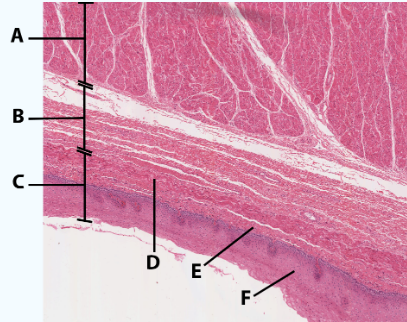

A

Muscularis

B

Submucosa

C

Mucosa

D

Muscularis mucosa

E

lamina propria

F

stratified squamous epithelial tissue

area

Esophagus